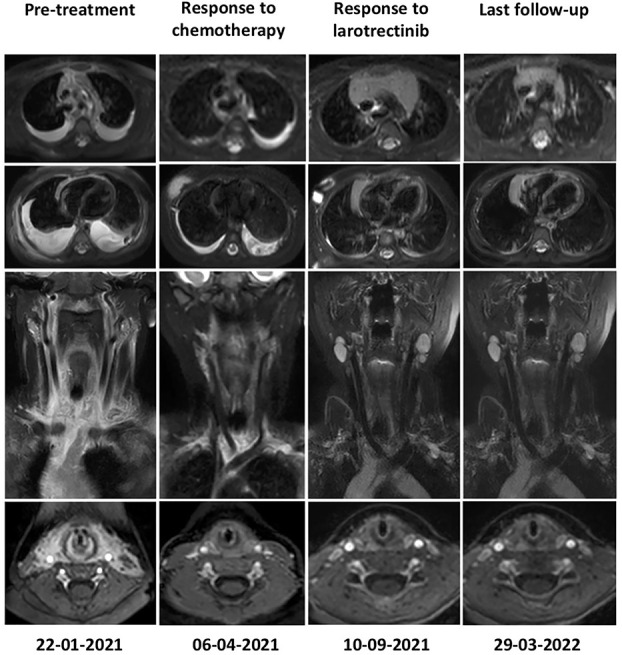

2021年4月,Anny开始每天2次口服拉罗替尼。

令所有人都没想到的是,拉罗替尼就像是这种恶性肿瘤的克星一样。接受拉罗替尼治疗后仅一周,体能状态评分就从治疗前的20分升到90分,Anny不再需要引流,顺利出院回家。

2个月的治疗后肿瘤实现了快速缓解。

2022年9月,Anny顺利完成17个月的治疗,肿瘤实现完全缓解(CR),体能评分达到100分!这意味着她的肿瘤全部消失了,截至文献发表时(2023年1月)仍持续处于完全缓解状态。她现在是一个健康快乐的3岁女孩。